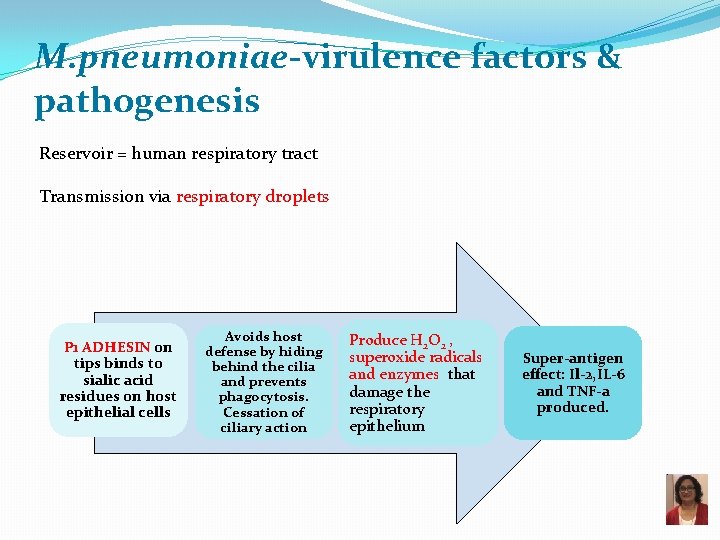

M. pneumoniae-virulence factors & pathogenesis Reservoir = human respiratory tract Transmission via respiratory droplets P 1 ADHESIN on tips binds to sialic acid residues on host epithelial cells Avoids host defense by hiding behind the cilia and prevents phagocytosis. Cessation of ciliary action Produce H 2 O 2 , superoxide radicals and enzymes that damage the respiratory epithelium Super-antigen effect: Il-2, IL-6 and TNF-a produced.